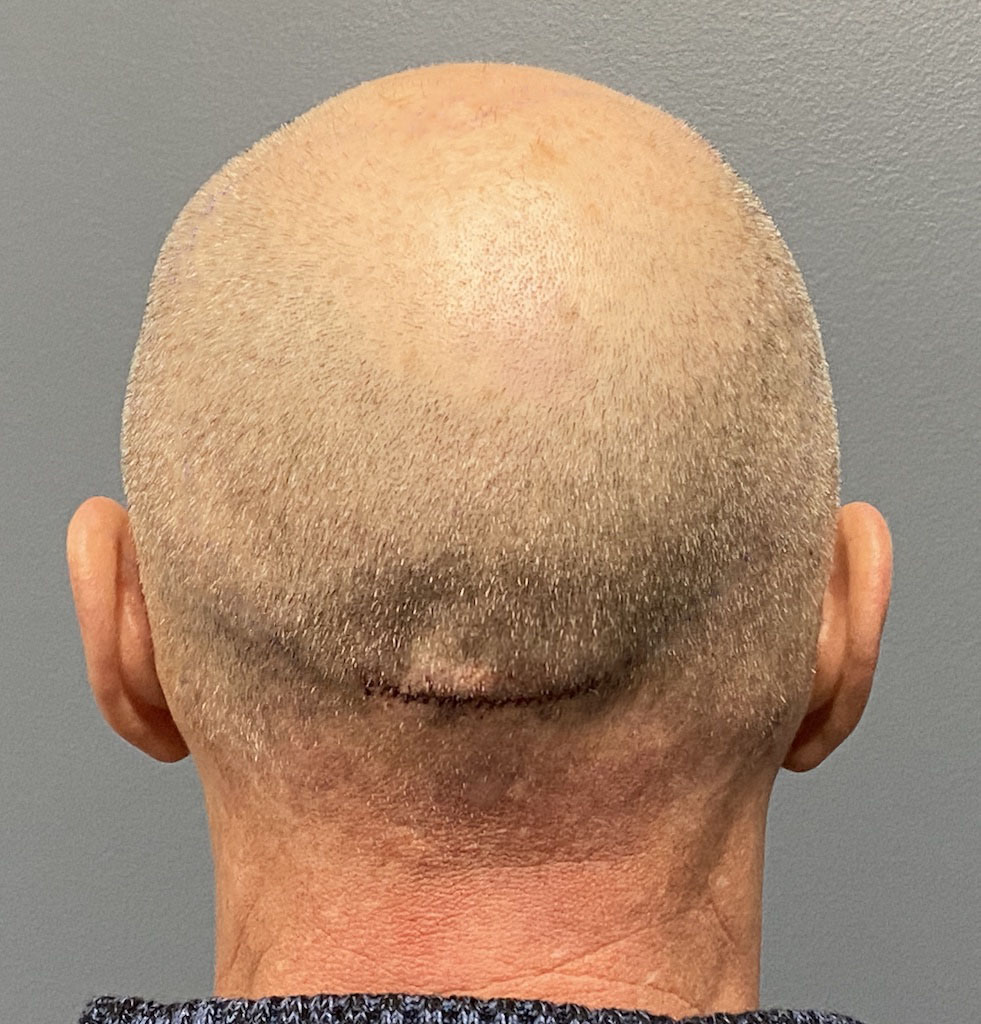

Patient 1

Desire for removal of occipital knob on back of skull.

Occipital knob skull reduction done through a small 3cm overlying skin incision.

Desire for removal of occipital knob on back of skull.

Occipital knob skull reduction done through a small 3cm overlying skin incision.